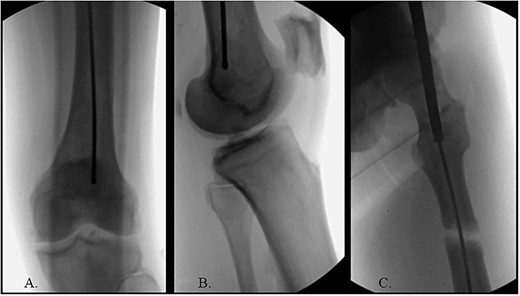

A 60-year-old male, who was diagnosed with Stage 4 prostate adenocarcinoma with known rib metastases and treated with chemotherapy and prostatectomy, sustained a pathologic left transverse subtrochanteric femur fracture after a ground-level fall while ascending stairs at his home. He denied any antecedent left hip or thigh pain. Radiographs revealed blastic metastatic lesions to his left femur (Fig. 1).

The patient was positioned supine on a fracture table. A guide wire was inserted through a 4-cm surgical incision proximal to the greater trochanter (GT) and was passed through a cannulated awl in a position slightly medial to the tip of the GT on the AP and center on the lateral (Fig. 2B). A (15-mm) entry reamer widened the opening (Fig. 2C). A rigid cannulated reduction rod and forceful malleting allowed the ball-tipped guidewire to cross the close reduced fracture, but too lateral and posterior distally (Fig. 3A and B). The cannulated flexible reamers encountered impassible blastic lesions within the proximal femur (Figs 3C and 5B).

(A) Cannulated awl positioned medial to tip of GT on the AP XR; (B) cannulated awl positioned center of GT on the lateral XR; (C) entry reamer over guide pin on the AP XR.

(A) Ball-tipped guidewire slightly lateral position at the knee on the AP XR; (B) ball-tipped guidewire too posterior at the knee on the lateral XR; (C) flexible reamer within the proximal femur abutting blastic lesions.